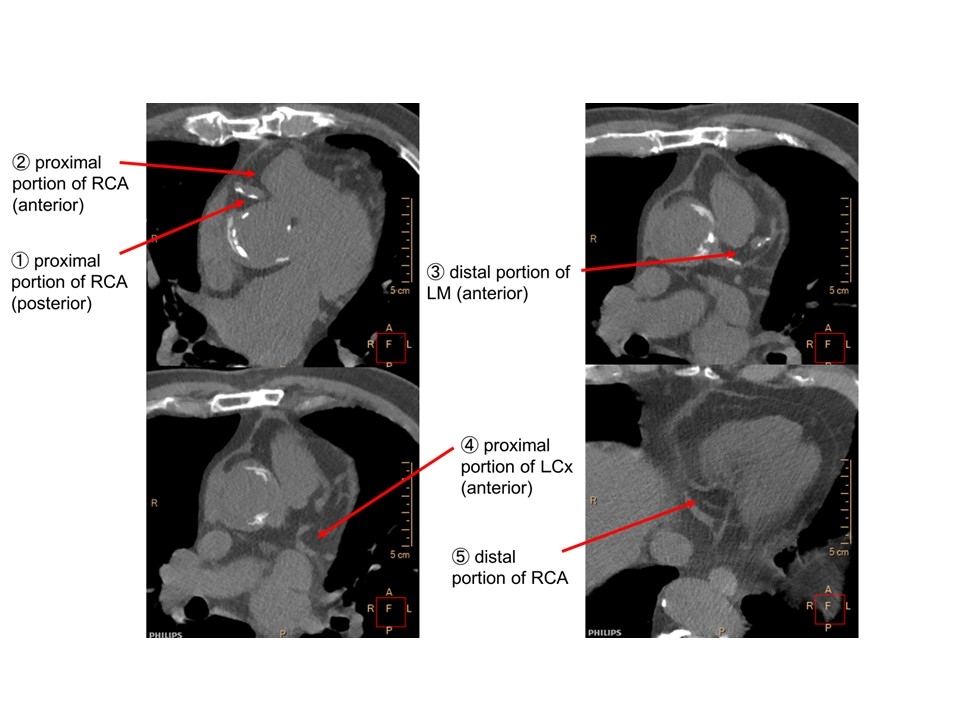

Methods: This is a retrospective analysis of 13 patients (eight males, 60±11 years), scheduled for pulmonary vein isolation, who underwent cardiac spectral CT (7500, Philips) and routine late-phase CT contrast acquisition to evaluate left atrial thrombi. From non-contrast and early- and late-contrast data, EANs and EDs (% relative to water) of PCATs were determined at five sites per patient, as well as coronary arterial plaques, on enhanced CT images.